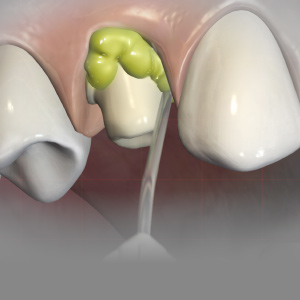

Proximal Resin Infiltration: Revolutionizing the Way We Treat Early Caries

Jeanette MacLean, DDS, DABPD, FAAPD

Friday, May 29, 2020

Resin infiltration is an evidence-based, nonsurgical treatment option for proximal and smooth-surface incipient carious lesions. This continuing education (CE) article will focus on how resin infiltration effectively bridges the gap between simply monitoring lesions and more invasive surgical treatm...